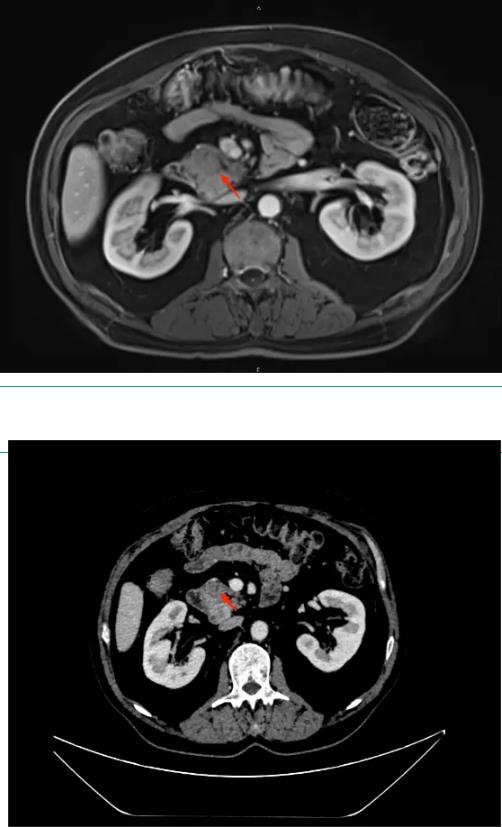

患者,男性,67岁,以“间断性腹痛6年,加重伴黑便4天”入院,腹部CT及MRI提示胰头钩突占位,考虑神经内分泌肿瘤可能性大,肝S2段占位,考虑肿瘤性病变;EUS提示胰腺钩突部可见一4.3*3.3cm大小实性占位,肝S2段可见2.1*1.7大小实性占位。行EUS-FNB病理结果回归提示神经内分泌瘤(NET G2)。